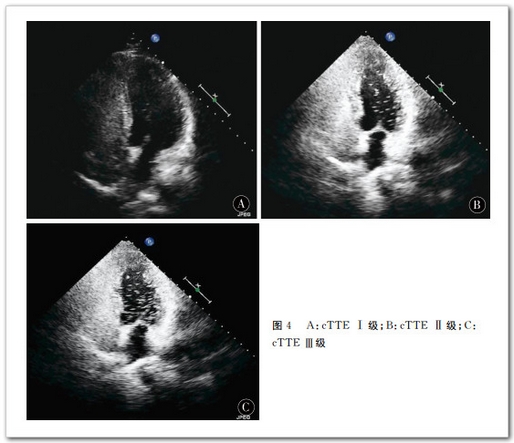

166 例 患 者 中 cTCD檢 測 出 RLS80 48.19%),cTTE 檢 測 出RLS68 40.96%),差異有統(tǒng)計(jì)學(xué)意義0.005)。cTCD靜息 狀 態(tài) 下 檢 測 出RLS2716.27%),Valsava動作后檢測出RLS8048.19%)。Valsava動作后 RLS檢出率明顯高于靜息狀態(tài)0.005)。cTTE靜 息 狀 態(tài) 下 檢 測 出 RLS2816.87%),Valsava動作后檢測出 RLS6841.76%)。Valsava動作后 RLS檢 出 率 明 顯 高 于 靜 息 狀 態(tài)0.005)。cTCD 半定量分級結(jié)果級少量分流2615.66%),級中量分流2615.66%),級大量分流2816.87%);cTTE半 定 量 分 級 結(jié) 果級少量分流2716.27%),級中量分流1911.45%),級大量分流2213.25%)。兩 種 檢 查 方 法 的 分 級 結(jié) 果 差 異 有 統(tǒng)計(jì)學(xué)意義Bowker檢驗(yàn)值14.818,=0.011),cTCDcTTE檢出 RLS級別高。